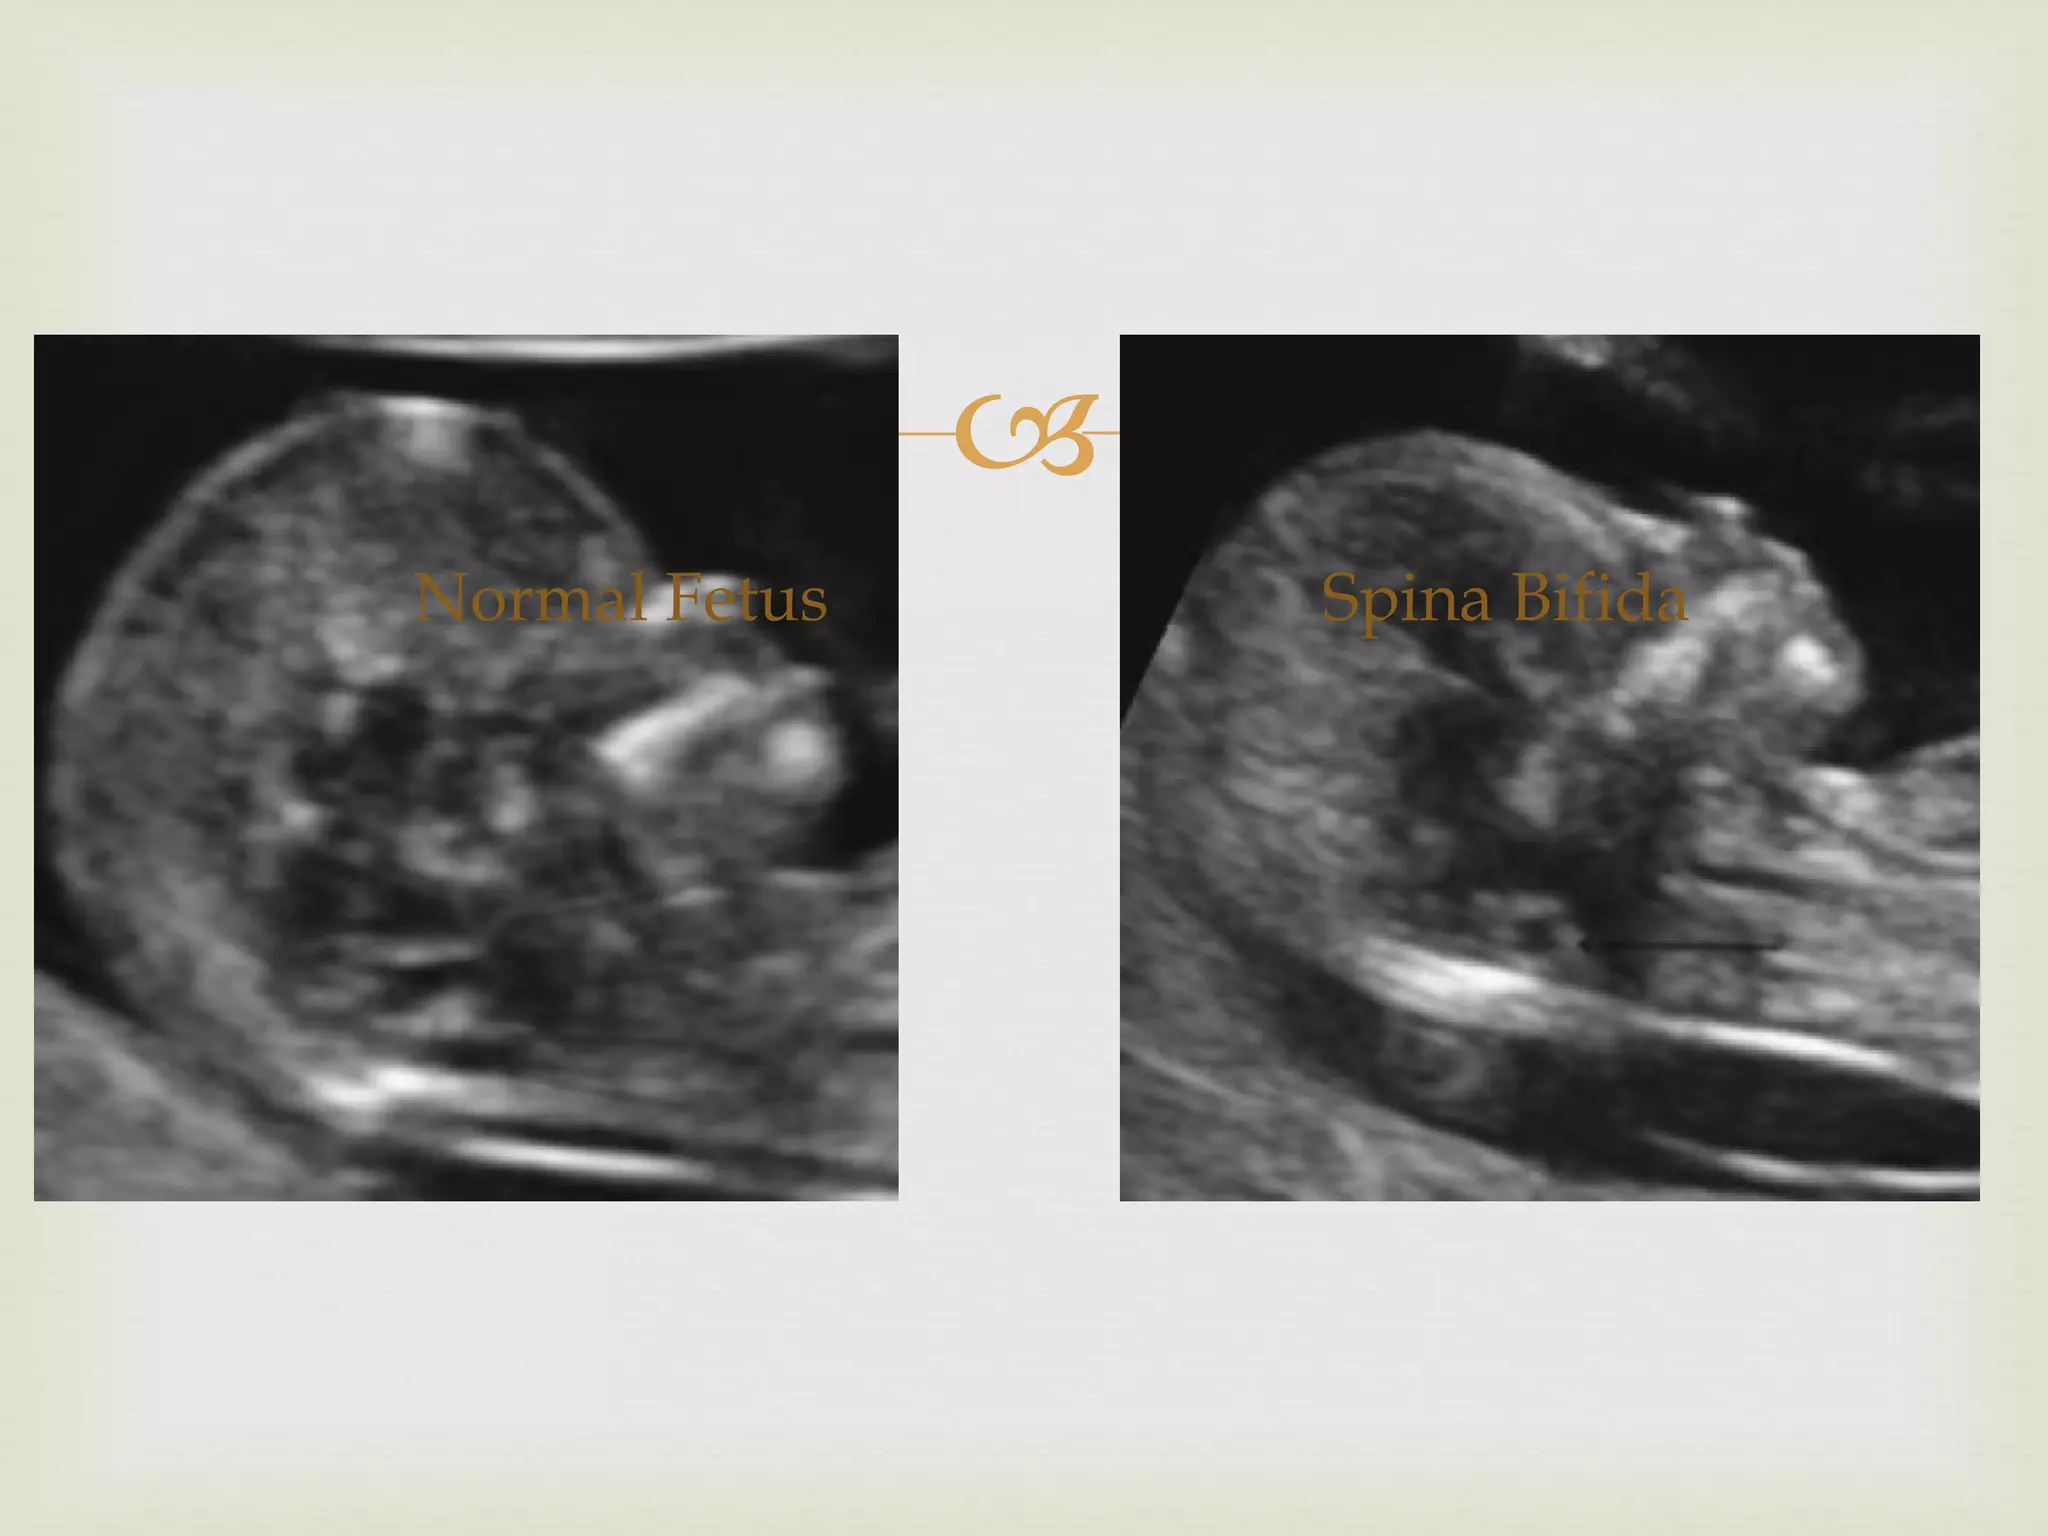

The position of  parallel peduncles  is visible Visualisation of cerebellum  is difficult before 14 weeks  & may be confused with choroid plexus of the IV ventricle In sagittal view, the fetuses demonstrated a  flat occiput In axial view, the frontal bones are not convex but were retracted giving “acorn shape”

The contours of the metencephalon in spina bifida are straighter than normal This could be due to downward displacement of the brain

Normal Fetus Spina Bifida